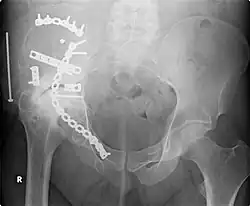

Orthopedic surgery or orthopedics (alternative spelling orthopaedics) is the branch of surgery concerned with conditions involving the musculoskeletal system.[1] Orthopedic surgeons use both surgical and nonsurgical means to treat musculoskeletal trauma, spine diseases, sports injuries, degenerative diseases, infections, tumors and congenital disorders.